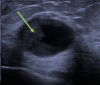

Results: 18 (33.3%) cases were pure EPC, 12 (22.2%) were EPC associated with ductal carcinoma in situ (DCIS) and 24 (44.4%) cases had concurrent invasive ductal carcinoma. EPCs were more likely to present as a solid-cystic mass on sonography (63.8%), regular-shaped (oval or round) (97.9%), lack spiculations (95.7%) and lack suspicious microcalcifications (95.6%). Median tumour size was largest in the EPC with IDC group (18.5 mm). 2 patients developed loco-regional recurrence. Overall survival is good for EPCs of all subtypes.